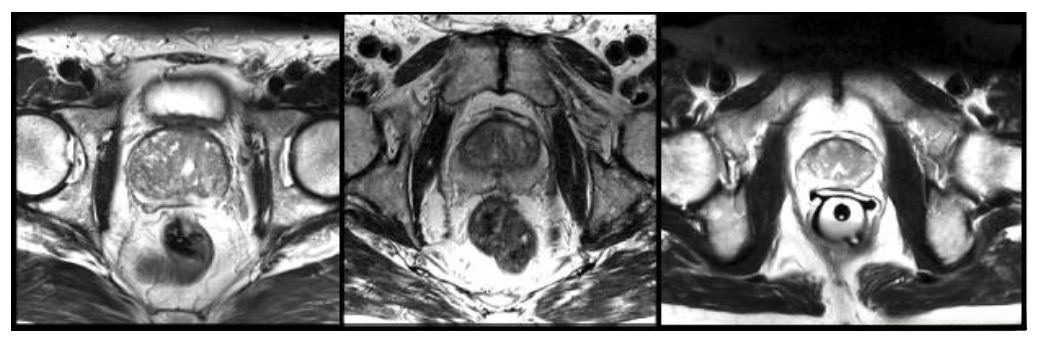

There were several medical data used in clinical practice consists of 3D volumes, such as MRI volumes illustrate prostate, while most approaches are only able to process 2D images. A 3D image segmentation based on a volumetric, fully convolutional neural network is proposed in this work.

Slices from MRI volumes depicting prostate

Prostate segmentation nevertheless is the crucial task having clinical relevance both during diagnosis, where the volume of the prostate needs to be assessed and during treatment planning, where the estimate of the anatomical boundary needs to be accurate.